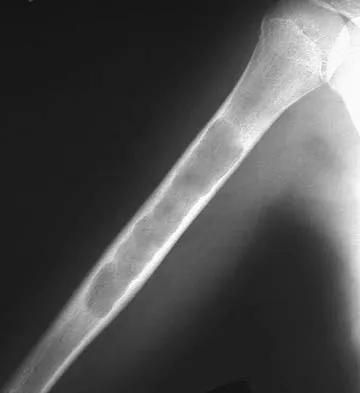

A 10-year-old boy with a history of retinoblastoma now reports right knee pain. AP and lateral radiographs are shown in Figures 3a and 3b. What is the most likely diagnosis?

Explanation

The radiographs show a bone-producing lesion in the femoral diaphysis. The radiographic appearance of small round cell tumors is more permeative with an elevated periosteum and no matrix production. The appearance of this lesion is most consistent with osteosarcoma. Patients who carry the Rb gene are predisposed to osteosarcoma. However, Ewing's sarcoma, primitive neuroectodermal tumor, and osteomyelitis can all occur in this location. Unni KK: Dahlin's Bone Tumors: General Aspects and Data on 11,087 Cases, ed 5. Philadelphia, PA, Lippincott-Raven, 1996, pp 143-160.

References:

- Chauveinc L, Mosseri V, Quintana E, Desjardins L, Schlienger P, Doz F, Dutrillaux B: Osteosarcoma following retinoblastoma: Age at onset and latency period. Ophthalmic Genet 2001;22:77-88.